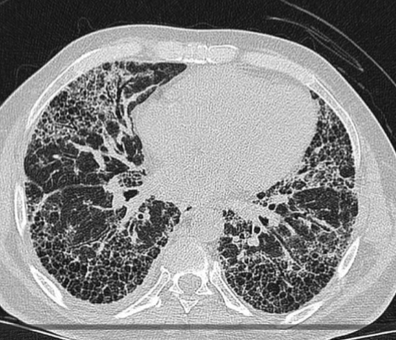

폐 섬유증은 폐에 염증이 반복되면서 정상적인 폐 조직이 점차 흉터 조직(섬유조직)으로 바뀌는 질환입니다. 이 섬유조직은 고무처럼 탄력이 없고 단단해, 한 번 형성되면 정상 폐로 되돌아가지 않는다는 특징이 있습니다. 이로 인해 폐가 충분히 팽창하지 못하고, 산소를 받아들이는 능력이 점점 떨어지게 됩니다.

이러한 변화 때문에 폐 섬유증은 단순 염증성 질환인 폐렴이나 기관지염과 달리, 진행성·비가역적인 폐 질환으로 분류됩니다.

✔ 흉부 CT에서 이상 소견이 나온 경우